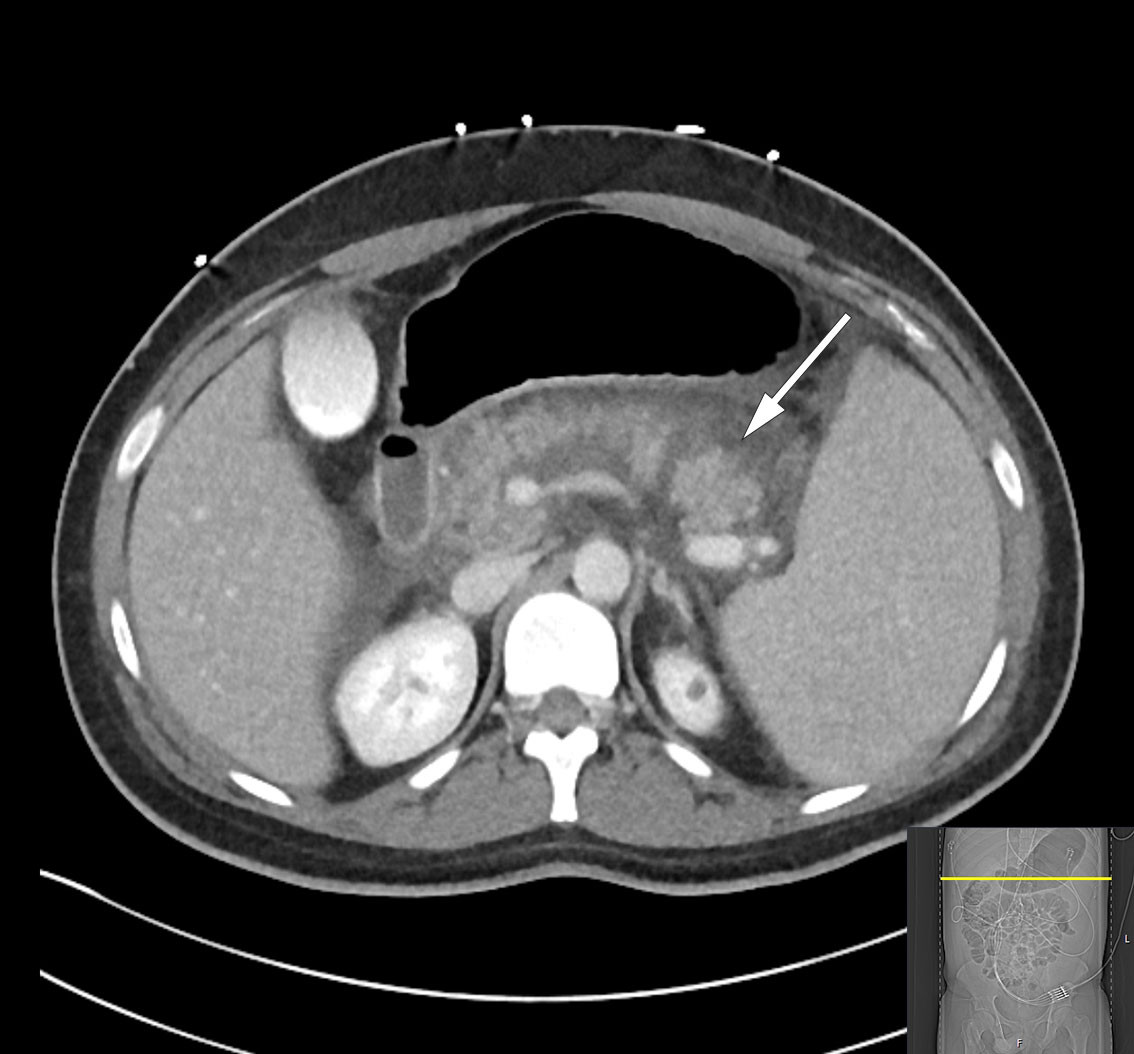

The following day, the patient was febrile with a temperature of 38.5°C but was stable on room air. The encapsulated necrosis was treated by inserting a Hot AXIOS lumen-apposing metal stent (LAMS), a system developed for endoscopic ultrasound-guided drainage of encapsulated necrosis via the stomach. A feeding tube was placed in the small intestine, and nutritional supplementation was initiated. Over the following days, the patient's clinical and biochemical status fluctuated. Broad-spectrum intravenous antibiotics were initiated in the form of meropenem 1 g three times daily due to an increase in CRP to 148 mg/L. In addition, a fall in haemoglobin to 6.9 g/dL led to the decision to transfuse the patient with three units of packed red cells. A CT scan, however, showed a significant reduction in the size of the encapsulated necrosis after placement of the stent, and showed the blood vessels to no longer be compressed (Figure 3). The patient underwent necrosectomy via gastroscopy, with removal of large amounts of dead tissue. Over the next few days, the patient was gradually mobilised, with accompanying improvements in respiration and good diuresis supported by loop diuretics. Two sets of blood cultures were sterile, while Staphylococcus epidermidis was detected in the urine but was of uncertain clinical significance. The epidural catheter was removed, and opioids were tapered in accordance with the patient's increasing mobility. The patient was then transferred to the gastroenterological surgery ward on day 10 of his third admission.